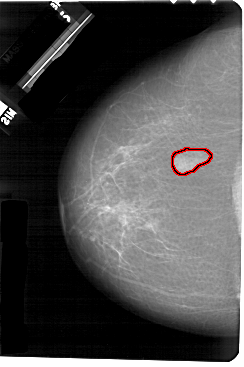

A_1266_1.LEFT_CC

LEFT_CC LINES 5491 PIXELS_PER_LINE 3646 BITS_PER_PIXEL 12 RESOLUTION 43.5 OVERLAY

FILE: A_1266_1.LEFT_CC.OVERLAY

TOTAL_ABNORMALITIES 1

ABNORMALITY 1

LESION_TYPE MASS SHAPE LOBULATED MARGINS ILL_DEFINED

ASSESSMENT 3

SUBTLETY 5

PATHOLOGY BENIGN

TOTAL_OUTLINES 1

BOUNDARY